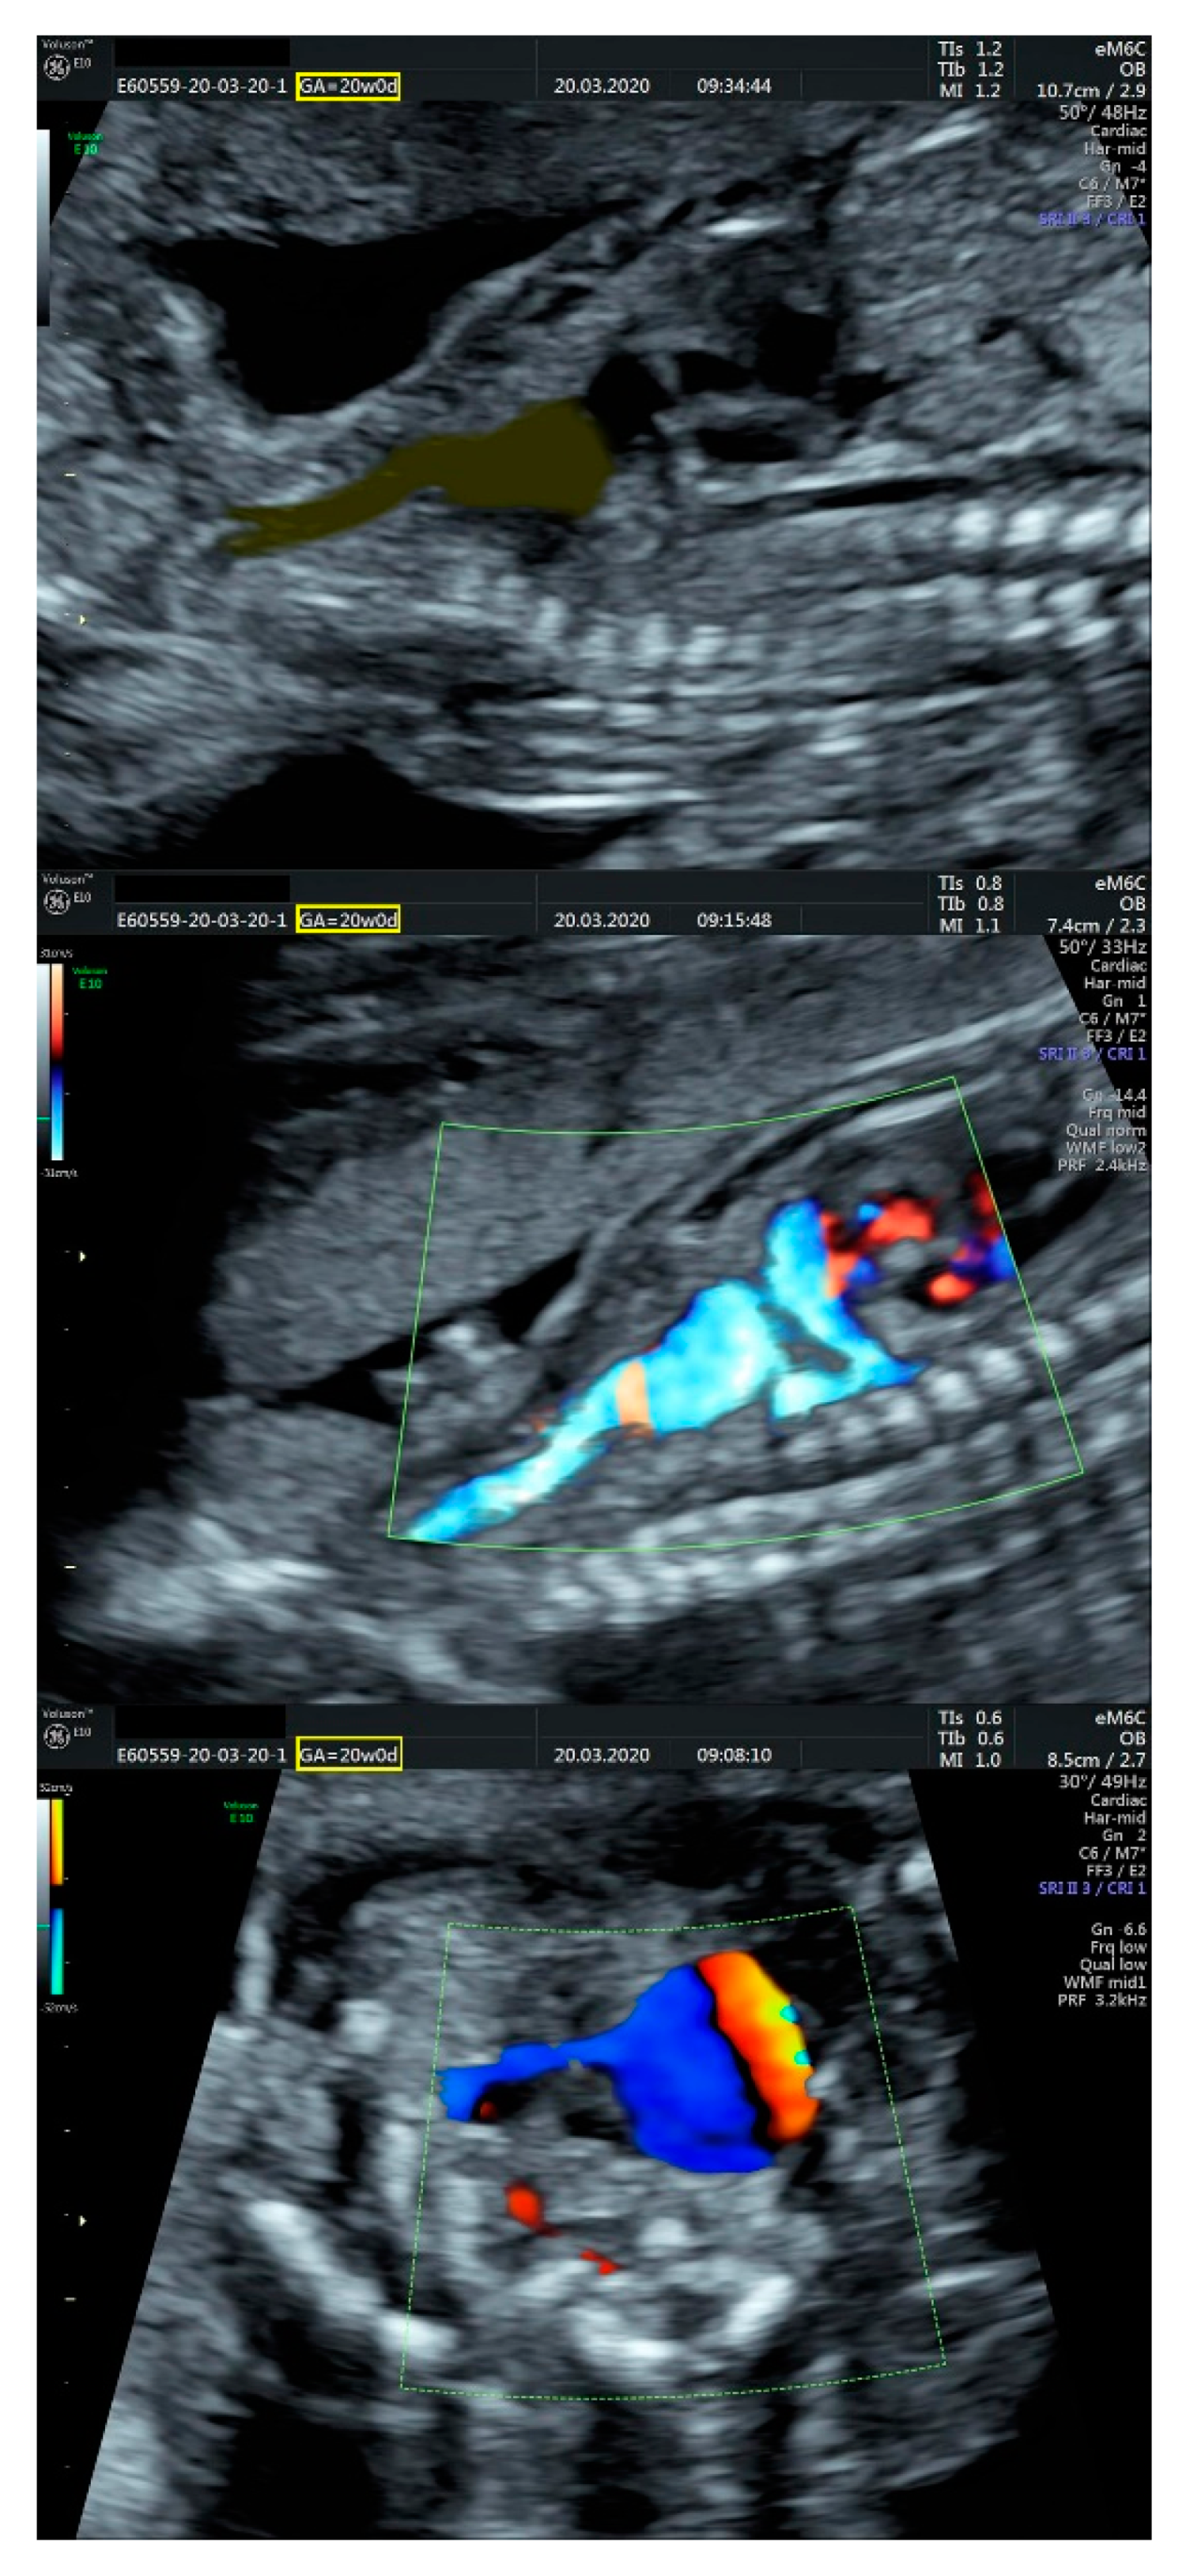

2.1. Ultrasound Findings

- an isolated aortic arch anomaly (supposedly aneurysmal dilation from which the left common carotid artery emerges) and coarctation of the aorta with the anterograde flow;

- ventricular septal defect, coarctation of the aorta, and a vascular formation located superior from the aortic arch with the appearance of an arteriovenous fistula;

- aneurysmal dilation located above the pulmonary trunk bifurcation and a dilated left common carotid artery with a retrograde flow;

- minor ventricular septal defect with a normal ductus venosus triphasic flow.